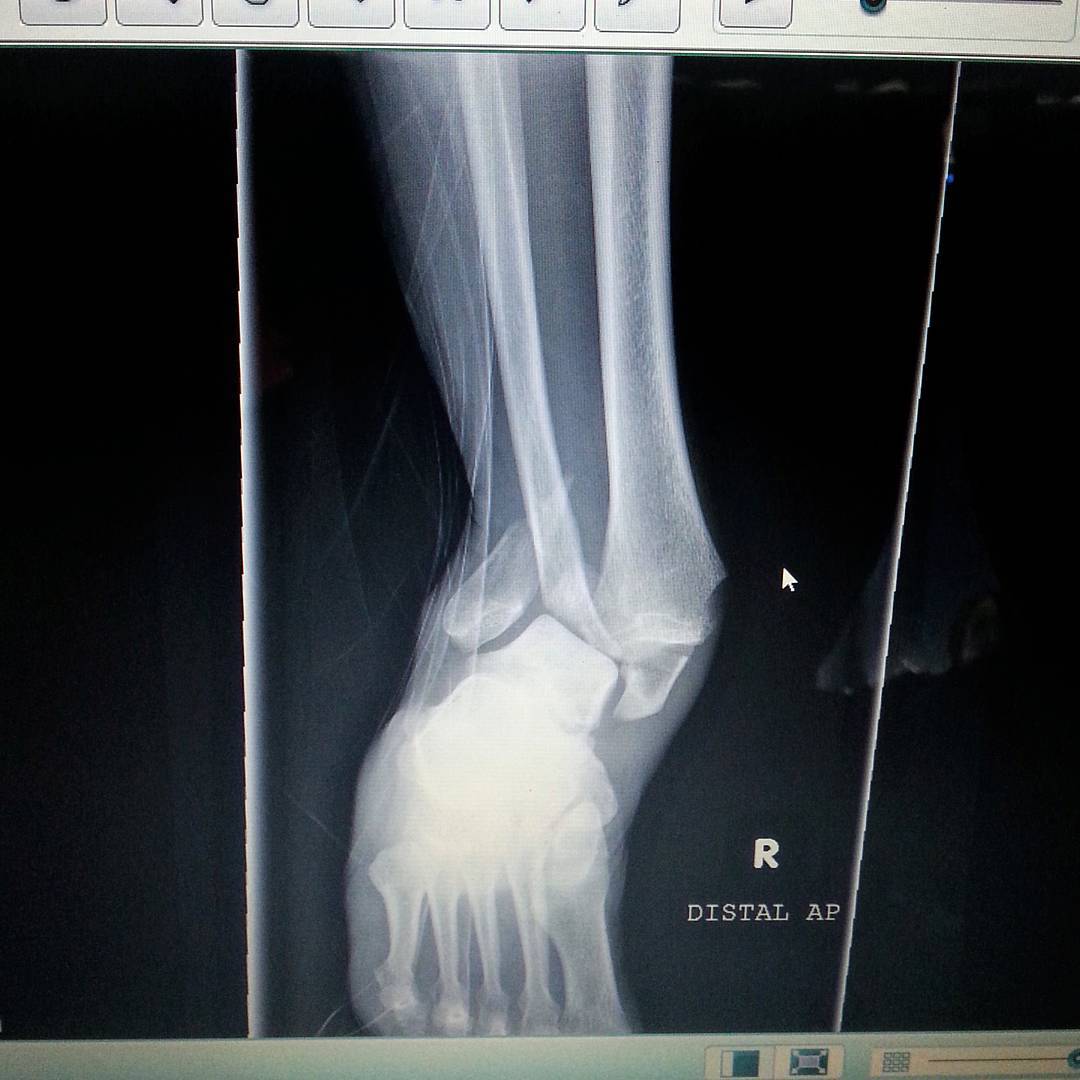

![]() |

| The x-ray showing the multiple fractures and severe dislocation. FYI: one’s ankle should not look like this… |

I made it to the Seward Emergency Room, a block from the trail head, 4 1/2 hours after the accident, arriving just after midnight. Although I had relatively no pain I was given and IV along with pain meds so they could assess my leg and take x-rays. Shortly after I was told that the damage was too severe for them to treat there and surgery would be required. The fog presented a problem as the medevac wouldn’t be able to fly until sun up. At one point the ER doctor got a little rise out of me when she talked about the possibility of a Coast Guard evacuation if it was necessary to save my limb.